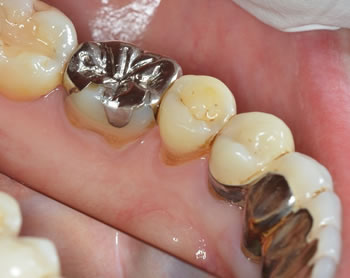

10年経過しておりますが、定期的にメンテナンスに来られており今でも歯肉の状態は安定しており問題ありません! |

反対側の左です、、、

さすがに歯肉退縮はしかたがありませんが、歯肉に炎症もなくメンテナンスされており、今後もこの状態を維持していきたいと思います! |